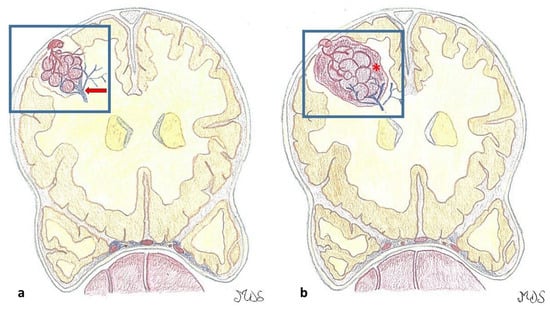

- Ruan, D.; Yu, X.-B.; Shrestha, S.; Wang, L.; Chen, G. The Role of Hemosiderin Excision in Seizure Outcome in Cerebral Cavernous Malformation Surgery: A Systematic Review and Meta-Analysis. PLoS ONE 2015, 10, e0136619. [Google Scholar] [CrossRef]

- Shang-Guan, H.-C.; Wu, Z.-Y.; Yao, P.-S.; Chen, G.-R.; Zheng, S.-F.; Kang, D.-Z. Is Extended Lesionectomy Needed for Patients with Cerebral Cavernous Malformations Presenting with Epilepsy? A Meta-Analysis. World Neurosurg. 2018, 120, e984–e990. [Google Scholar] [CrossRef]

- Baumann, C.R.; Schuknecht, B.; Lo Russo, G.; Cossu, M.; Citterio, A.; Andermann, F.; Siegel, A.M. Seizure Outcome after Resection of Cavernous Malformations Is Better When Surrounding Hemosiderin-Stained Brain Also Is Removed. Epilepsia 2006, 47, 563–566. [Google Scholar] [CrossRef] [PubMed]

- Wang, X.; Tao, Z.; You, C.; Li, Q.; Liu, Y. Extended Resection of Hemosiderin Fringe Is Better for Seizure Outcome: A Study in Patients with Cavernous Malformation Associated with Refractory Epilepsy. Neurol. India 2013, 61, 288–292. [Google Scholar] [CrossRef] [PubMed]

- Dammann, P.; Schaller, C.; Sure, U. Should We Resect Peri-Lesional Hemosiderin Deposits When Performing Lesionectomy in Patients with Cavernoma-Related Epilepsy (CRE)? Neurosurg. Rev. 2017, 40, 39–43. [Google Scholar] [CrossRef] [PubMed]